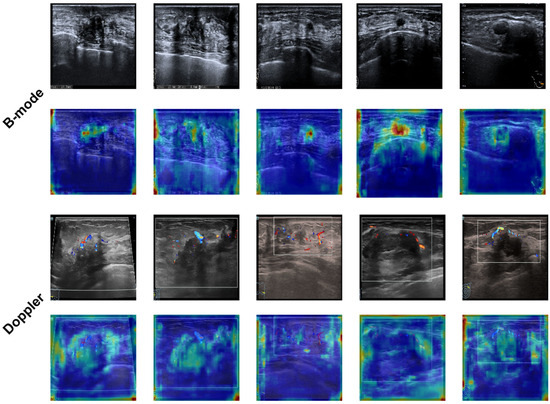

- Imaging Model: Deep learning models (including EfficientNet, ResNet101, and ViT) were developed and validated exclusively on Cohort A, utilizing the B-mode and Doppler ultrasound images. A weighted loss function was employed during training to mitigate the effects of class imbalance. This approach assigned higher penalties for misclassifying minority (invasive) class samples, thereby compelling the models to pay closer attention to these critical, less frequent instances.